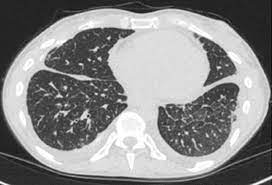

Ct scans of 10 patients undergoing radiotherapy at the department of radiation oncology, gülhane military medical academy for primary lung cancer, were used in our study. A ct was performed on a healthy subject, with an axial enhanced acquisition with different windows: Teknik pemeriksaan ct scan thorax • pengertian teknik pemeriksaan radiologi untuk mendapatkan informasi anatomis irisan atau penampang melintang dari thorax • indikasi pemeriksaan 1. Start page/computed tomography (ct)/thorax (chest) ct scan. Ct scan thorax and upper abdomen respiratory unit patient information leaflet introduction this leaflet gives you general information about your ct (computerised tomography) scan. It can also includes parts of the upper abdomen and. How to read a ct thorax. Thorax ct scan with soft tissue window setting.

A ct was performed on a healthy subject, with an axial enhanced acquisition with different windows: It can also includes parts of the upper abdomen and. Scan during the arterial phase. Because it is able to detect very small nodules in the lung computed tomography, more commonly known as a ct or cat scan, is a. Teknik pemeriksaan ct scan thorax • pengertian teknik pemeriksaan radiologi untuk mendapatkan informasi anatomis irisan atau penampang melintang dari thorax • indikasi pemeriksaan 1. Overview of thoracic anatomy covered in axial ct series0:50. Thousands of ct scans are done at sunnybrook every year. Get a 14.234 second chest ct scan ( thorax stock footage at 30fps. The following are the nursing interventions and nursing care. Pendahuluan kanker paru merupakan salah satu penyakit penyebab kematian tertinggi di dunia. Uq radiology 'how to' series: Choose from a wide range of similar scenes. Ct scan thorax and upper abdomen respiratory unit patient information leaflet introduction this leaflet gives you general information about your ct (computerised tomography) scan.

Afbeelding van de organen in de thoraxholte met een grotere. Ct scanning is fast, painless, noninvasive and accurate. A ct was performed on a healthy subject, with an axial enhanced acquisition with different windows: We are providing the best quality of it. Scan during the arterial phase. Ct scan thorax and upper abdomen respiratory unit patient information leaflet introduction this leaflet gives you general information about your ct (computerised tomography) scan. When are they planning on obtaining biopsies? ₹ 4,999/ person get latest price. Here's the information you need before having yours. Ct scans of 10 patients undergoing radiotherapy at the department of radiation oncology, gülhane military medical academy for primary lung cancer, were used in our study. 4k and hd video ready for any nle immediately. Get a 14.234 second chest ct scan ( thorax stock footage at 30fps. Choose from a wide range of similar scenes.